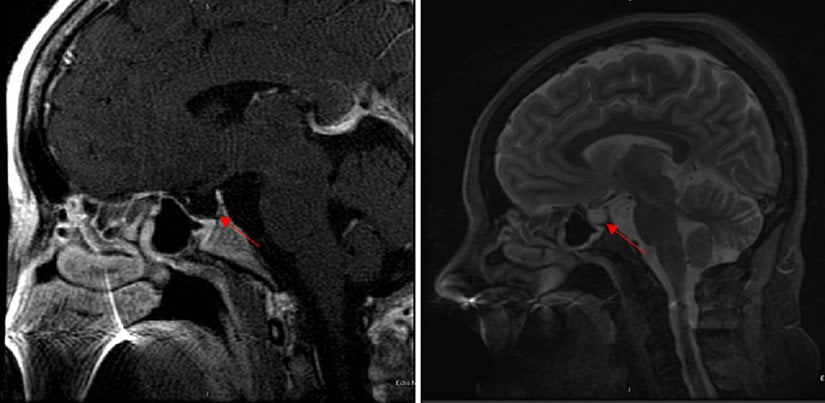

Tanıyı doğrulamak için MRI görüntülemesi kullanılır. Radyolojik inceleme sonucunda boş sella (%70) veya kısmen boş sella (%30) görüntülenebilir.[6]